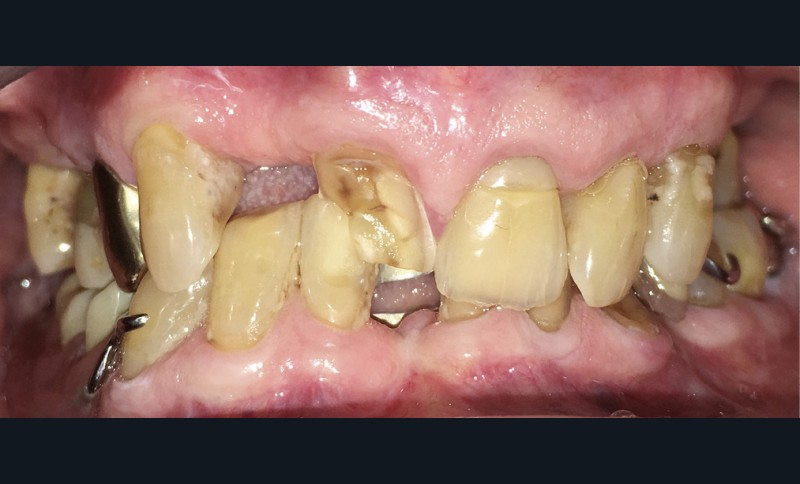

Le maxillaire présente un édentement de classe III subdivision 2 de Kennedy-Applegate (K-A). La 12 est absente et la 11 fracturée. 24-25-26 ont été extraites depuis longtemps (fig. 3a). 15 et 17 sont dépulpées et restaurées avec des composites anciens mais non infiltrés.

À la mandibule, une prothèse partielle à armature métallique conçue selon les critères ayant fait l’objet d’un large consensus, compense un édentement de classe II, subdivision 3…